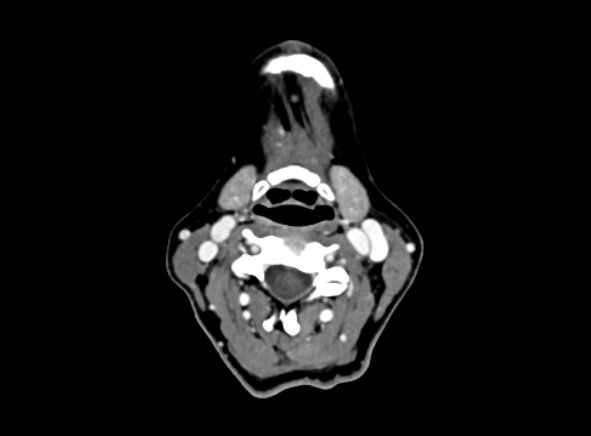

@Ihurt see attached your annotated imaging.

Looks like both your IJVs are compressed. But your right IJV looks worse. In this specific slice, it appears your right ijv (left side of image) is compressed between your styloid and C1, and may sort of be wrapping along the side of C1. This aligns with the 3D imaging you showed earlier with your right IJV. Like @Rex said, it’s sometimes hard to know which vascular structure is what without having the full imaging and being able to follow it. I’m usually quite good, but your right side is throwing me off, not sure if there’s a lack of contrast or things are super jumbled. I’ve attached my own imaging to help show you the landmarks to compare with your own. I highly suggest watching my tutorial on CT imaging for the axial view - just type “axial CT tutorial” in the forum and you’ll find it. It’s a ~15min video where I help you locate and follow vascular structures. I’m not a radiologist but I hope it can help.

Your left IJV has some compression, which looks to have only C1 involved (at least at this frame.

Whenever there is IJV compression there is likely vagus nerve compression/irritation as well.